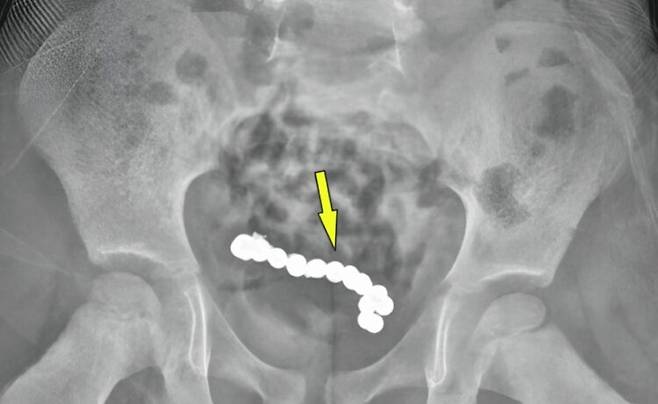

소하르병원 의료진은 남아에게 다시 복부 엑스레이 촬영을 했고, 그 결과 둥근 이물질들이 사슬처럼 연결돼있는 것이 보였다.

이를 제거하기 위한 수술에서 의료진은 총 22개의 자석을 발견했다. 자석들은 서로 붙어 고리 모양을 이루고 있었다. 자석 때문에 장 일부가 괴사해 천공(구멍)이 발생한 상태여서 손상된 장 부위 약 15cm를 절제하고 다시 이어붙이는 문합 수술을 진행했다.